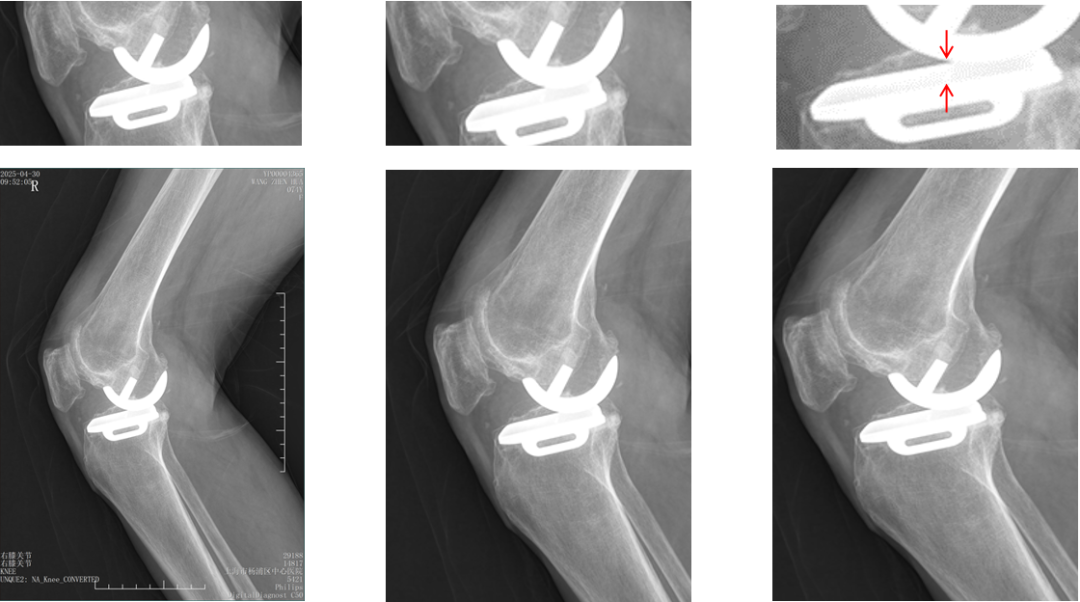

Bearing脱位在正位片上显示股骨与胫骨假体关节面接触,侧位片显示bearing位于关节囊前方或者后方。

病例3:Bearing 陈旧性前脱位2年

病例3:Bearing 陈旧性前脱位的处理